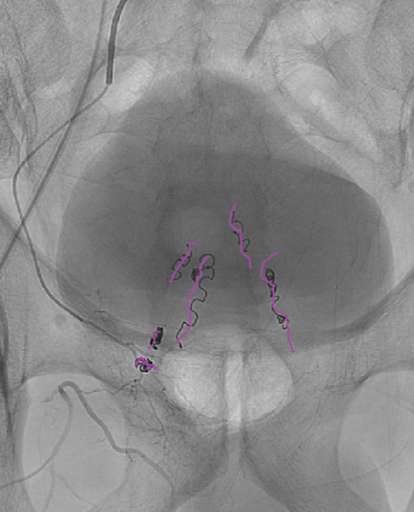

תמונות מהפעולה:

בתמונה הראשונה, שלב האבחון, רואים באדום את העורקים המזינים את הרקטום, מלמעלה זה עורק ה-INFERIOR MESENTERIC ARTERY ומימין זהו עורק ה-MIDDLE RECTAL ARTERY.

חשוב לחסום את העורק הנוסף מימין כשרואים אותו גדוש, ללא החסימה שיעור החזרה של הטחורים גבוה.

התמונה השניה, שלב הטיפול, בסגול סלילים שהוחדרו לאחר הזרקת החלקיקים בכל כלי דם רלוונטי: